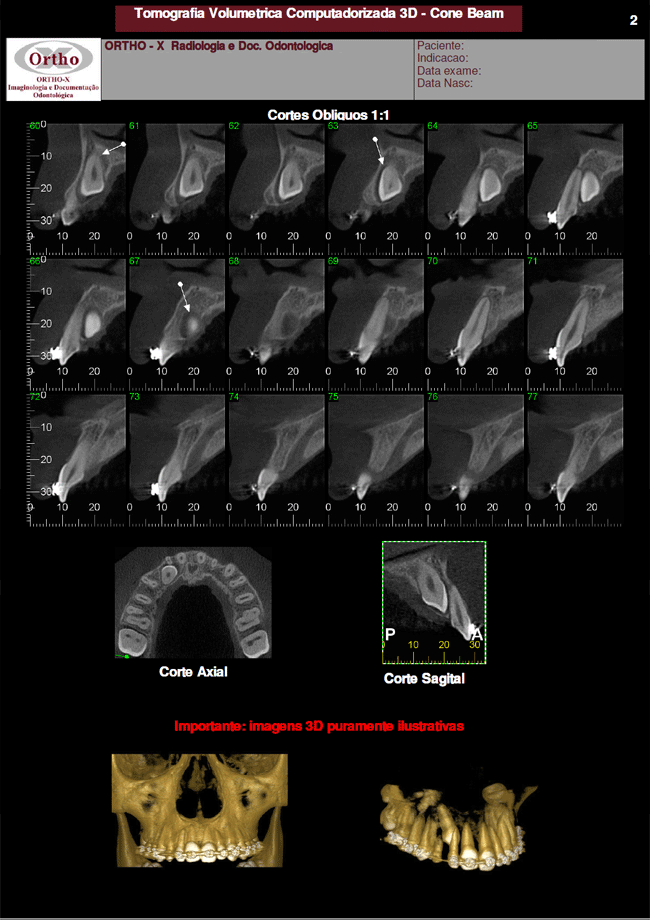

Exames > Tomografia Computadorizada 3D > Exemplo de Exames: Dente Incluso

Exemplo de Exames: Dente Incluso